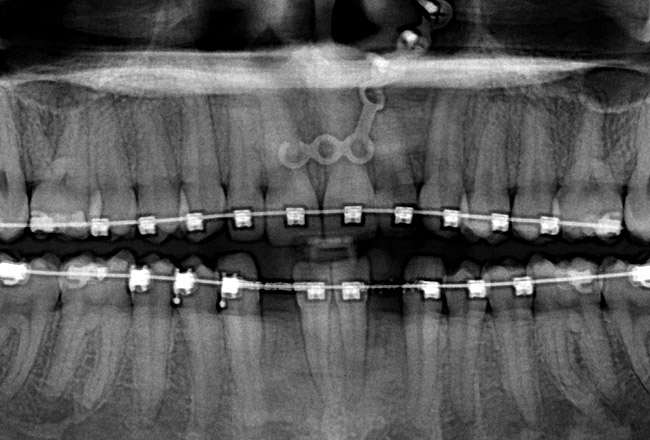

Fig 24 (through Fig 26). A 50-year-old female concerned about appearance and bite. Jackscrew appliance was placed after 6 months of orthodontic alignment.

Fig 25. A 50-year-old female concerned about appearance and bite. Jackscrew appliance was placed after 6 months of orthodontic alignment.

Fig 26. A 50-year-old female concerned about appearance and bite. Jackscrew appliance was placed after 6 months of orthodontic alignment.

Fig 27. Patient was missing tooth No. 11 and had A-P and transverse maxillary deficiencies with anterior and left posterior crossbites. Bite was opened with glass ionomer cement. Single-tooth osteotomies were performed on teeth Nos. 6 and 12 and multiple-tooth osteotomies were completed on teeth Nos. 3 to 4, 7 to 10, and 13 to 14.

Fig 28. Corticotomies were also performed on Nos. 7 to 10 segment. Postsurgery 21 days.

Fig 29 (through Fig 32). Jackscrews were activated 0.5 mm/day after 5-day latency period. Note pure translation of segments without tipping. Result 8 months postsurgery. Tooth No. 12 was converted to a canine, and an implant was placed in regenerate bone. Note amount of alveoloskeletal correction and increase in volume of maxillary arch. Also note the amount of protraction of maxillary anterior segments while anchorage was maintained in posterior segment. Restorative dentist: Michael E. Carter, DDS.

Fig 30. Jackscrews were activated 0.5 mm/day after 5-day latency period. Note pure translation of segments without tipping. Result 8 months postsurgery. Tooth No. 12 was converted to a canine, and an implant was placed in regenerate bone. Note amount of alveoloskeletal correction and increase in volume of maxillary arch. Also note the amount of protraction of maxillary anterior segments while anchorage was maintained in posterior segment. Restorative dentist: Michael E. Carter, DDS.